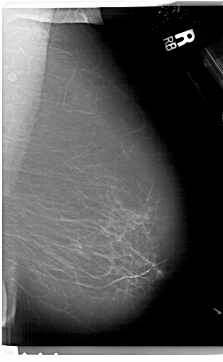

A_1627_1.LEFT_MLO

LEFT_MLO LINES 6871 PIXELS_PER_LINE 3961 BITS_PER_PIXEL 12 RESOLUTION 43.5 OVERLAY

FILE: A_1627_1.LEFT_MLO.OVERLAY

TOTAL_ABNORMALITIES 1

ABNORMALITY 1

LESION_TYPE MASS SHAPE IRREGULAR MARGINS ILL_DEFINED

ASSESSMENT 4

SUBTLETY 2

PATHOLOGY MALIGNANT